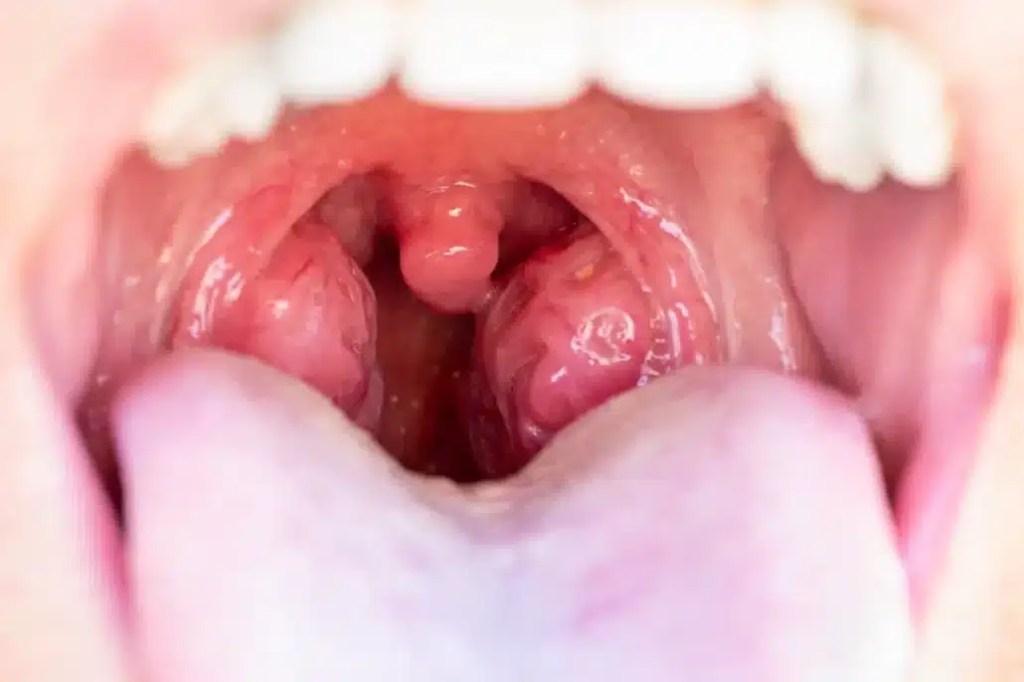

Antes de entender más de los tonsilolitos, hay que entender qué son las amígdalas. Se trata de estructuras linfoides situadas en la parte posterior de la garganta, específicamente en la región de la faringe. Son parte del sistema linfático y cumplen un rol esencial en la defensa inmunológica del cuerpo.

Actúan como una primera línea de defensa contra bacterias, virus y otras partículas que ingresan a través de la boca y la nariz. Gracias a su ubicación estratégica, las amígdalas atrapan estos patógenos y los eliminan, protegiendo al organismo de infecciones.

Dentro de las amígdalas, se encuentran las criptas amigdalinas, depresiones o cavidades donde los residuos de células muertas, bacterias y restos de alimentos pueden acumularse. A lo largo del tiempo, estos detritos pueden calcificarse debido a la interacción con sales de calcio presentes en la saliva, dando origen a los tonsilolitos.

- Inflamación amigdalina: En algunos casos, los tonsilolitos pueden causar inflamación de las amígdalas, acompañada de enrojecimiento y sensibilidad.